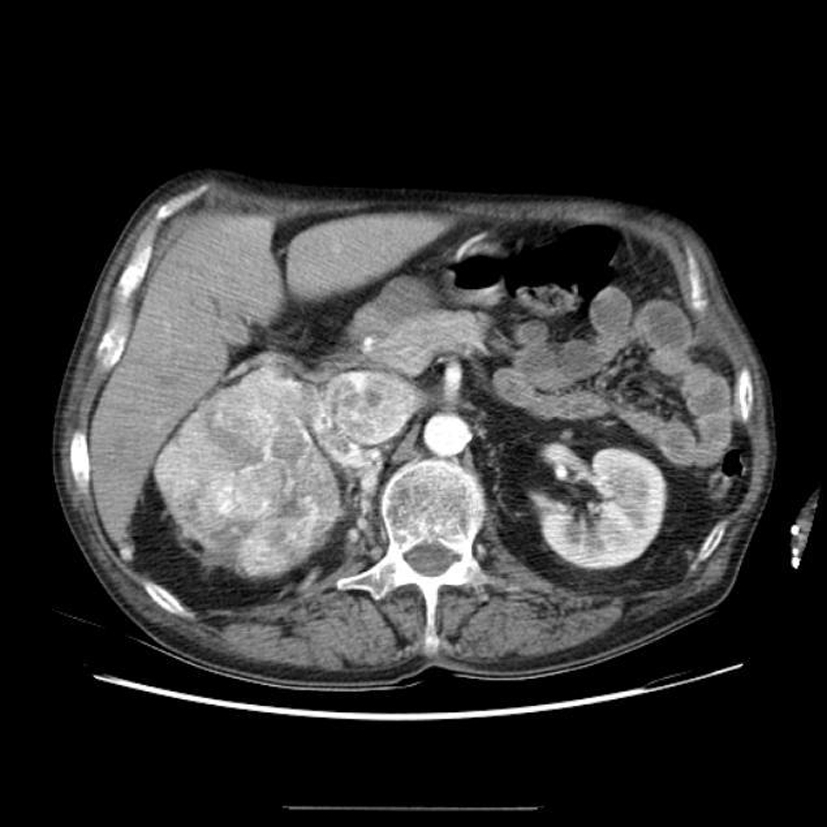

Diagnostic?

volumineuse tumeur rénale droite